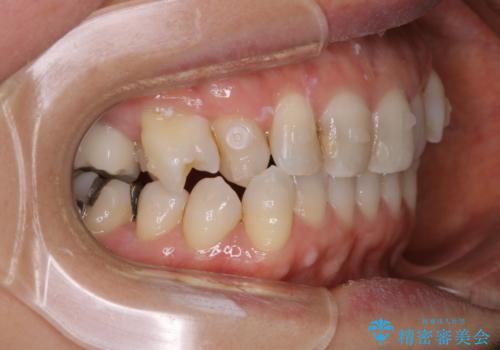

90度捻じれてしまい、完全にはみ出している歯を抜かずにインビザラインで治す。一般治療もできる精密審美会だからこその治療

- 右上の小臼歯が二本とも90度捻じれてしまっており、奥歯の噛み合わせに問題が生じていました。

今回は右上の奥歯に入っていた銀歯の形が悪く、そのせいで歯を並べるスペースが足りない状態でした。

右上の歯の被せ物を作りなおし、適切な歯の大きさに代えてあげることによってスペースを作りました。

また、それだけではスペースが足りない為右上の奥歯は遠心移動を行っています。